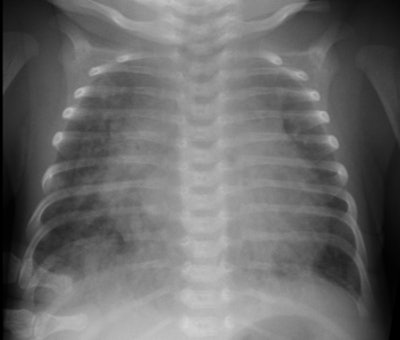

Endocardial cushion defect: 22 d patient presented with SOB. Note cardiac enlargement and marked increased vascularity in the lungs (shunt vascularity). Cardiac echo revealed an endocardial cushion defect. The patient did not have Down's syndrome. (Click image to enlarge) |

On CXR there is shunt vascularity and LAE (due to mitral valve incompetence), coupled with right heart enlargement. A "gooseneck sign" is characteristic on angiography- it is caused by a deficiency of both the conus and sinus portions of the interventricular septum, with narrowing of the left ventricular outflow tract [2]. The concavity of the interventricular septum below the mitral valve, along with elongation and narrowing of the LV outflow tract, produces a characteristic shape "gooseneck" shape on the AP projection at angiography [2].